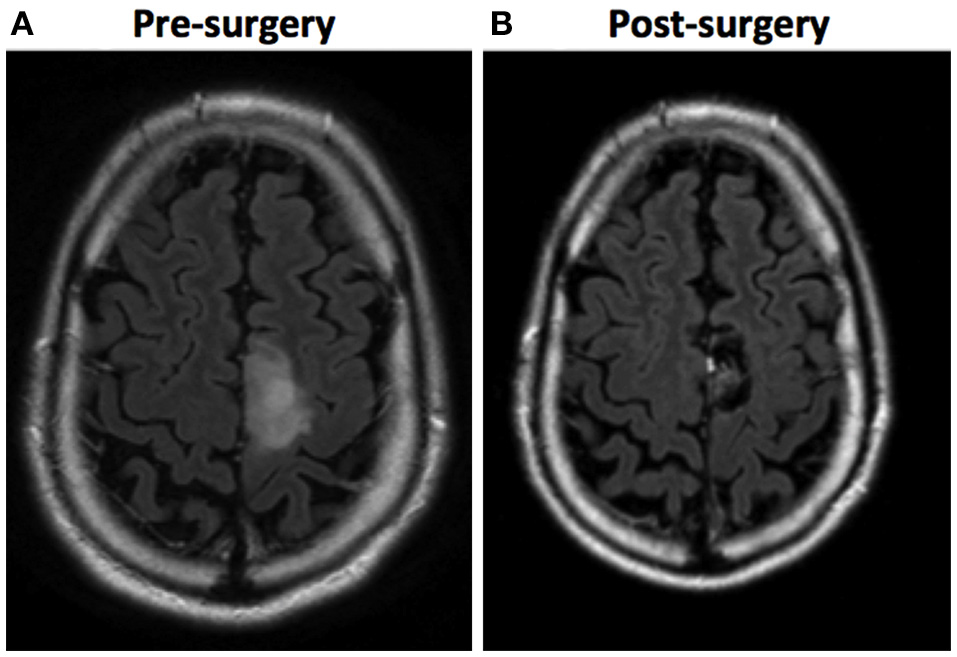

Figure 2

Example of an SMA lesion (in these images, left is right and right is left). (A) A FLAIR sequence MRI shows a tumoral lesion involving the left SMA in a 35-year-old patient. (B) A FLAIR sequence MRI 6 months after surgery shows a complete resection, achieved by performing awake brain mapping surgery. The pathology report was anaplastic oligodendroglioma.